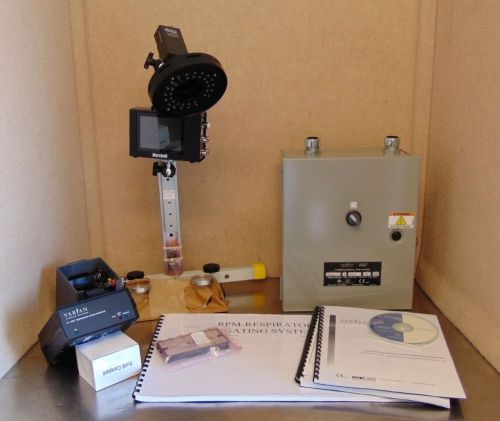

Brand | Philips |

| Model | HDI 5000 |